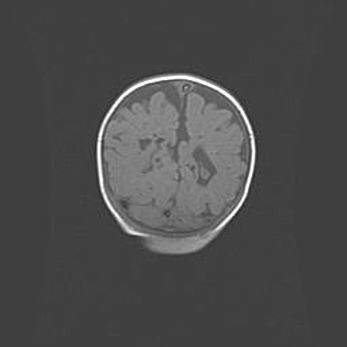

Множественные кисты обоих полушарий головного мозга, наибольшая из них в правой затылочной области. Ассиметричная атрофическая гидроцефалия.

Возраст: 7 месяцев

Вес: 5660 г

Пол: мужской

Окружность головы: 41,5 см

Срок гестации: 28-29 недель

Кисты головного мозга развиваются в результате многоочаговых некрозов вещества мозга и возникают вследствие перенесенной перинатальной инфекции, менингитов, энцефалитов, асфиксии, родовой травмы, расстройств мозгового кровообращения различного генеза. Образованию кист в веществе головного мозга плодов и новорожденных способствуют такие факторы, как высокое содержание в нем воды, недостаточная (или отсутствие) миелинизация и слабая астроглиальная реакция на повреждение.

Кисты могут сочетаться с гидроцефалией и другими поражениями головного мозга.